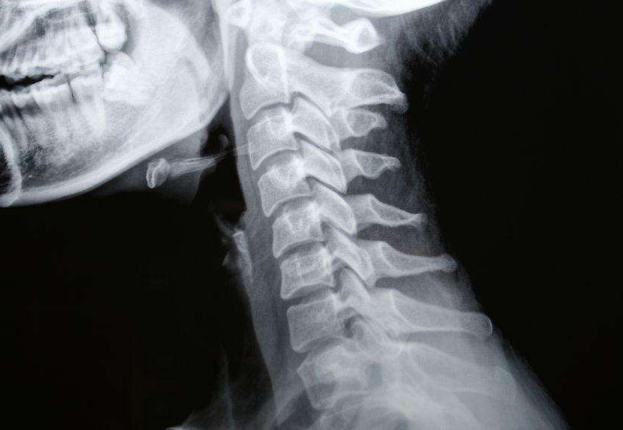

頸椎病圖片